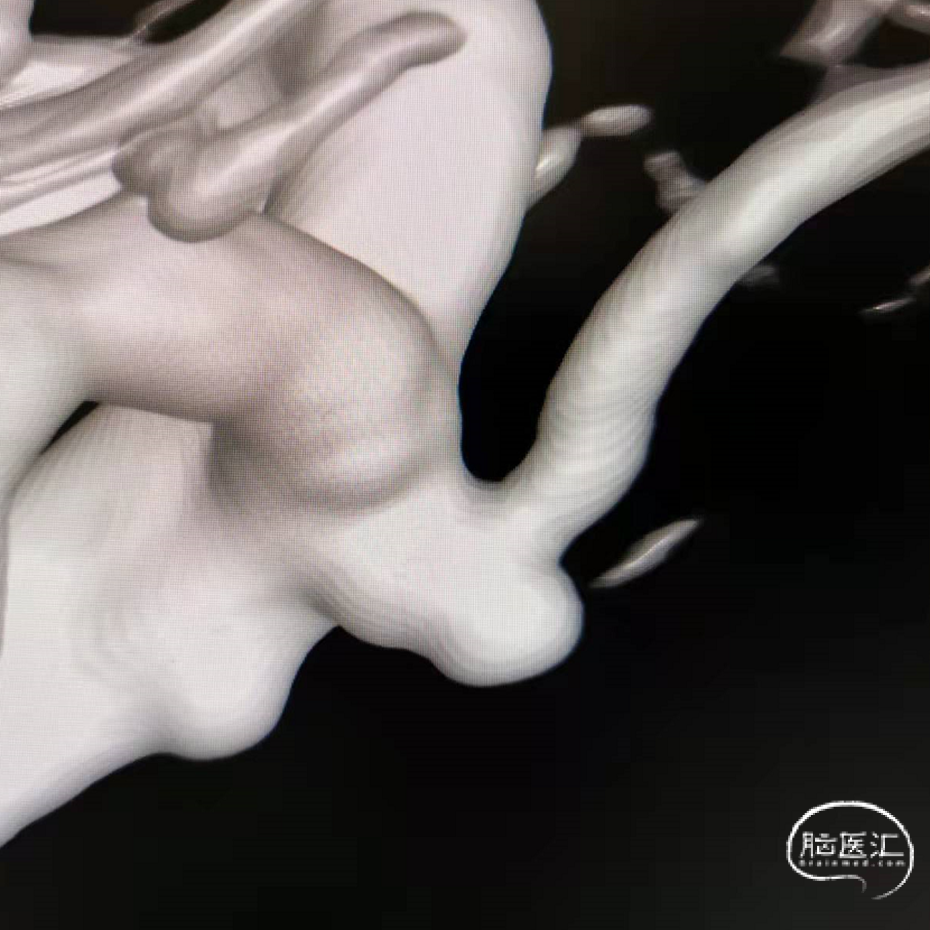

DSA三维重建

术后3D重建:动脉瘤不显影,载瘤动脉通畅

支架和弹簧圈重建的形态